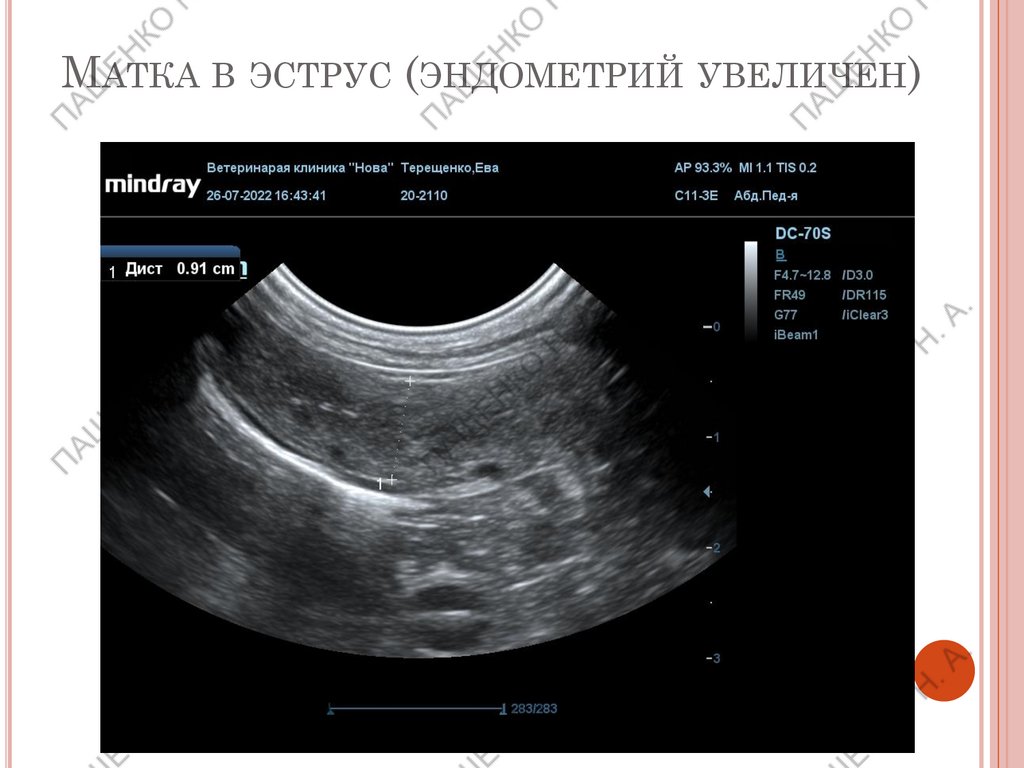

МАТКА В ЭСТРУС (ЭНДОМЕТРИЙ УВЕЛИЧЕН)

Проэструс, эструс или ранний диэструс –

стенка матки толще на 1-3 мм чем в анэструс

В течение эструса и диэструса эхогенность

стенки снижена.

Возможен незначительный просвет в теле

матки, но только до овуляции. Далее уже

считается патологией.